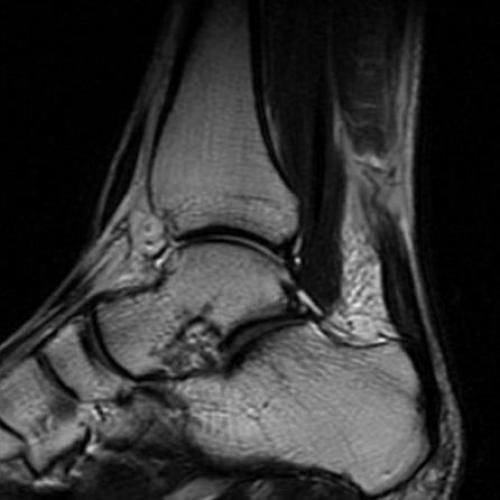

Клинический осмотр и применение диагностических тестов позволяют точно установить диагноз у 70% больных. На помощь специалисту приходят такие методы как сонография (УЗИ) и МРТ. Сонография – очень точный, быстрый, малоинвазивный и дешёвый метод диагностики разрывов ахиллова сухожилия – но только в руках опытного специалиста. Позволяет отличить частичные и полные разрывы.

Опытный специалист может быть с успехом заменён на качественное программное обеспечение и использование высокопольного МРТ.

В хронических случаях определяется атрофия мышц голени (камболовидной и икроножной), но дефект часто не определяется уже через 1-2 недели после травмы, так как он заполняется грануляционной тканью. Сила подошвенного толчка при этом не восстанавливается, так как длина ахиллова сухожилия значительно увеличивается, что делает невозможной передачу тяги икроножной мышцы.